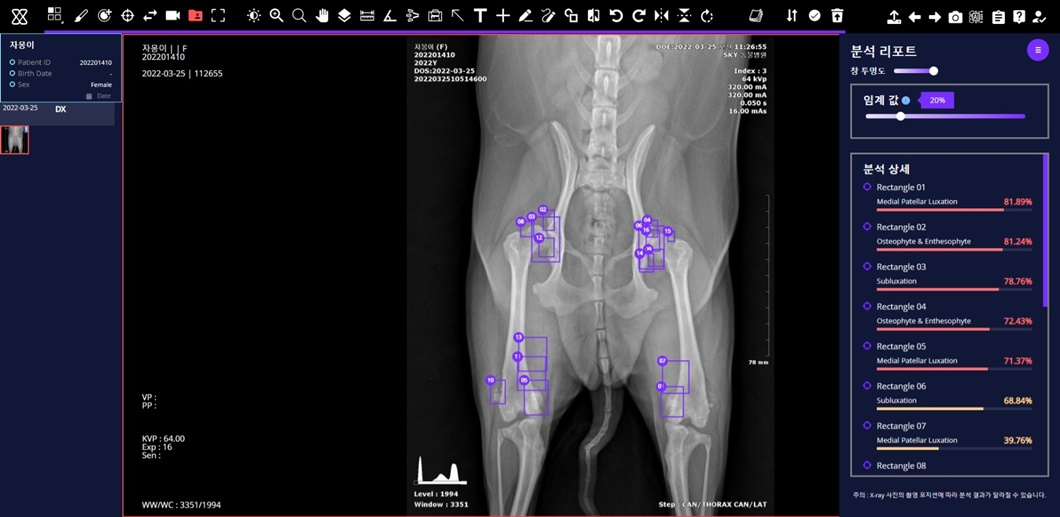

세부적으로는 ▲반려견 근골격 이상 영역 7종 검출모델 평균 질환탐지율(민감도)* 86% ▲반려견 흉부 이상 패턴 10종 분류모델 평균 질환탐지률(민감도) 84% ▲반려견 VHS(심장크기측정∙Vertebral Heart Scale) 측정모델 정확도* 97%를 기록했다.

‘엑스칼리버’를 통해 분석한 반려견의 근골격 엑스레이 사진.